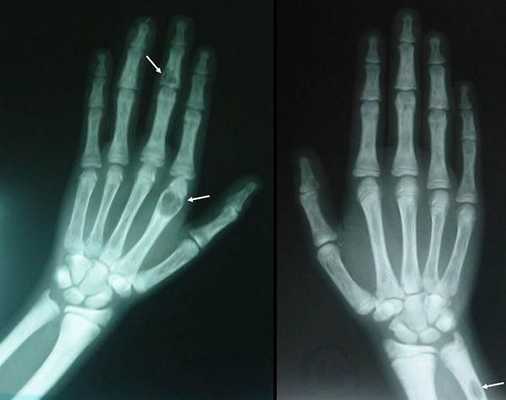

Длительное течение заболевания сказывается на формировании костей. Так, н а поздних стадиях вовремя не диагностированного гиперпаратиреоза наблюдаются:

- разрушение дистальных или концевых фаланг конечностей;

- сужение дистального отдела ключиц;

- очаги разрушения костей черепа;

- бурые опухоли длинных костей.